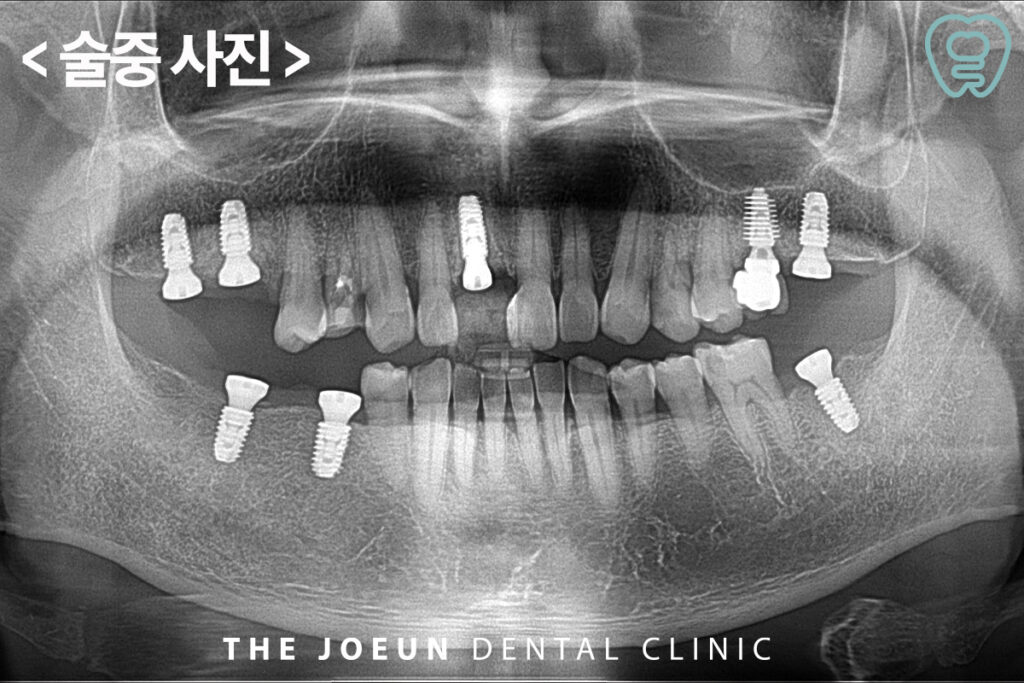

기존에 신경치료가 되어 있는데 염증이 생긴 오른쪽 앞니와 어금니를 발치하고 나머지 상실 부위에 임플란트를 바로 식립하였습니다.

발치 후 즉시 식립은 치아를 발치한 당일 해당 자리에 바로 임플란트를 심는 방식으로 발치된 부위의 자연적인 치유력을 활용하여 잇몸뼈 결합을 유도할 수 있다는 특징을 가지고 있는데요. 또한 치아를 뽑은 직후에는 잇몸 주변 조직의 회복력이 가장 활발한 시기이므로 잇몸뼈의 위축을 줄이고 형태를 비교적 자연스럽게 유지하는데 도움을 줄 수 있습니다. 다만 모든 경우에 즉시 식립이 가능한 것이 아니므로 달서구치과 전문 의료진의 정밀한 진단이 반드시 필요합니다.